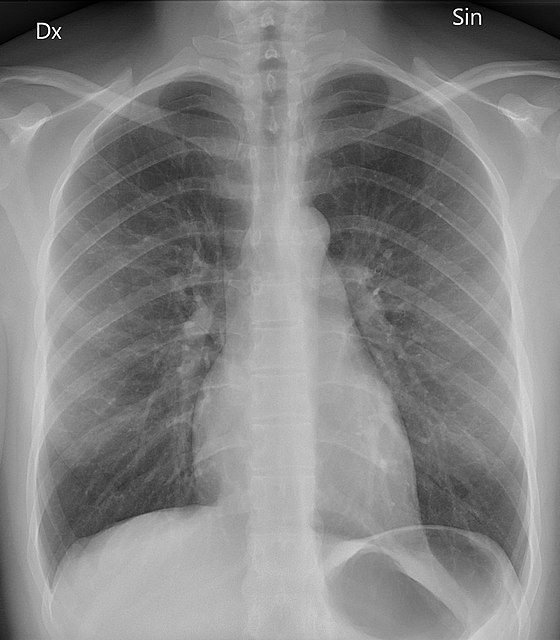

Bilateral lung abnormalities

Comparing sides does not always give the answer. The lungs may be abnormal on both sides and so awareness of the normal appearances of lung parenchyma becomes more important.

Bilaterally abnormal lung zones

- Multiple bilateral lung nodules

- Symmetrical distribution

- More nodules at the lung bases

Clinical information

- Shortness of breath, weight loss and clinically suspected underlying malignancy

Diagnosis

- Pulmonary metastases